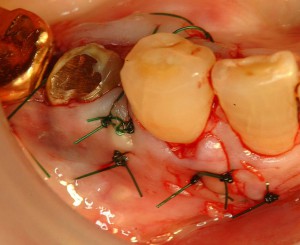

縫合

縫合